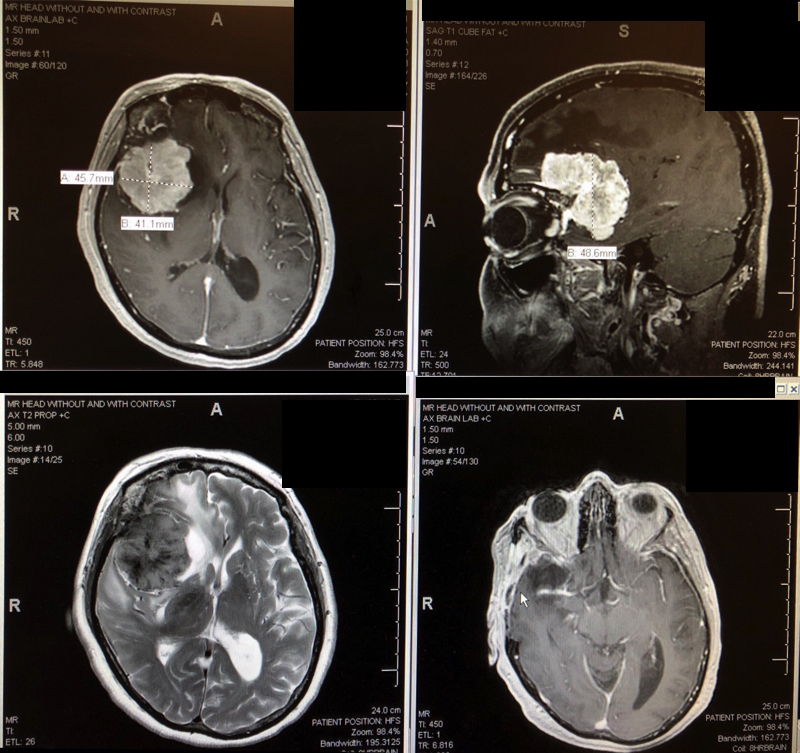

Top and bottom left: brain tumor before surgery. Bottom right: after surgery.